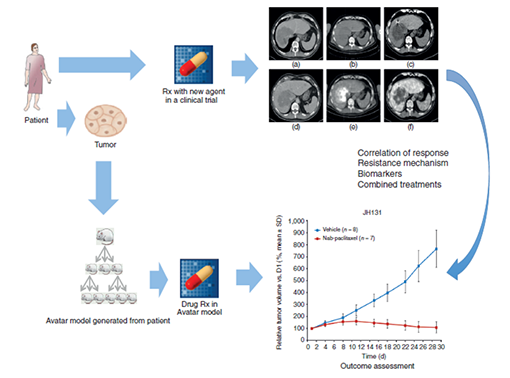

PDX模型(人源肿瘤异种移植模型)可以建立理想的肿瘤免疫疗法评价模型。beats365的PDX模型研究包括分子水平的基因分型以及肿瘤模型的药理药效评价服务,为临床药效研究提供了高度预测性的模型。

FAQsPDX(Patient-Derived Tumor Xenograft)模型是将来源于患者肿瘤的组织块直接移植到免疫缺陷型鼠上(如肾包膜下、皮下或原位)而建立的人源肿瘤异种移植模型。

PDX模型通过直接将患者肿瘤组织块移植到免疫缺陷鼠上,避免了体外培养过程中对肿瘤细胞的筛选,从而全面保全了肿瘤原有的生物学特性及其内在的异质性。

在传代过程中,PDX模型能够保持分子生物学水平的稳定,确保肿瘤细胞的遗传信息和表达模式得到很好的传递,为长期观察和药物筛选奠定坚实基础。

除了肿瘤细胞外,PDX模型还保留了肿瘤组织原有的非肿瘤基质和微环境,这对于理解肿瘤与宿主间的相互作用、肿瘤生长与转移机制至关重要。

由于PDX模型在多个方面高度模拟了临床病人肿瘤的特征,因此其研究结果具有更高的临床转化潜力,为肿瘤治疗方案的制定提供了更加可靠的科学依据。

1. 药理药效研究

通过PDX模型,beats365可提供各种药物(包括ADC、抗体、细胞疗法、PROTAC、分子胶等)的药理药效评价服务。